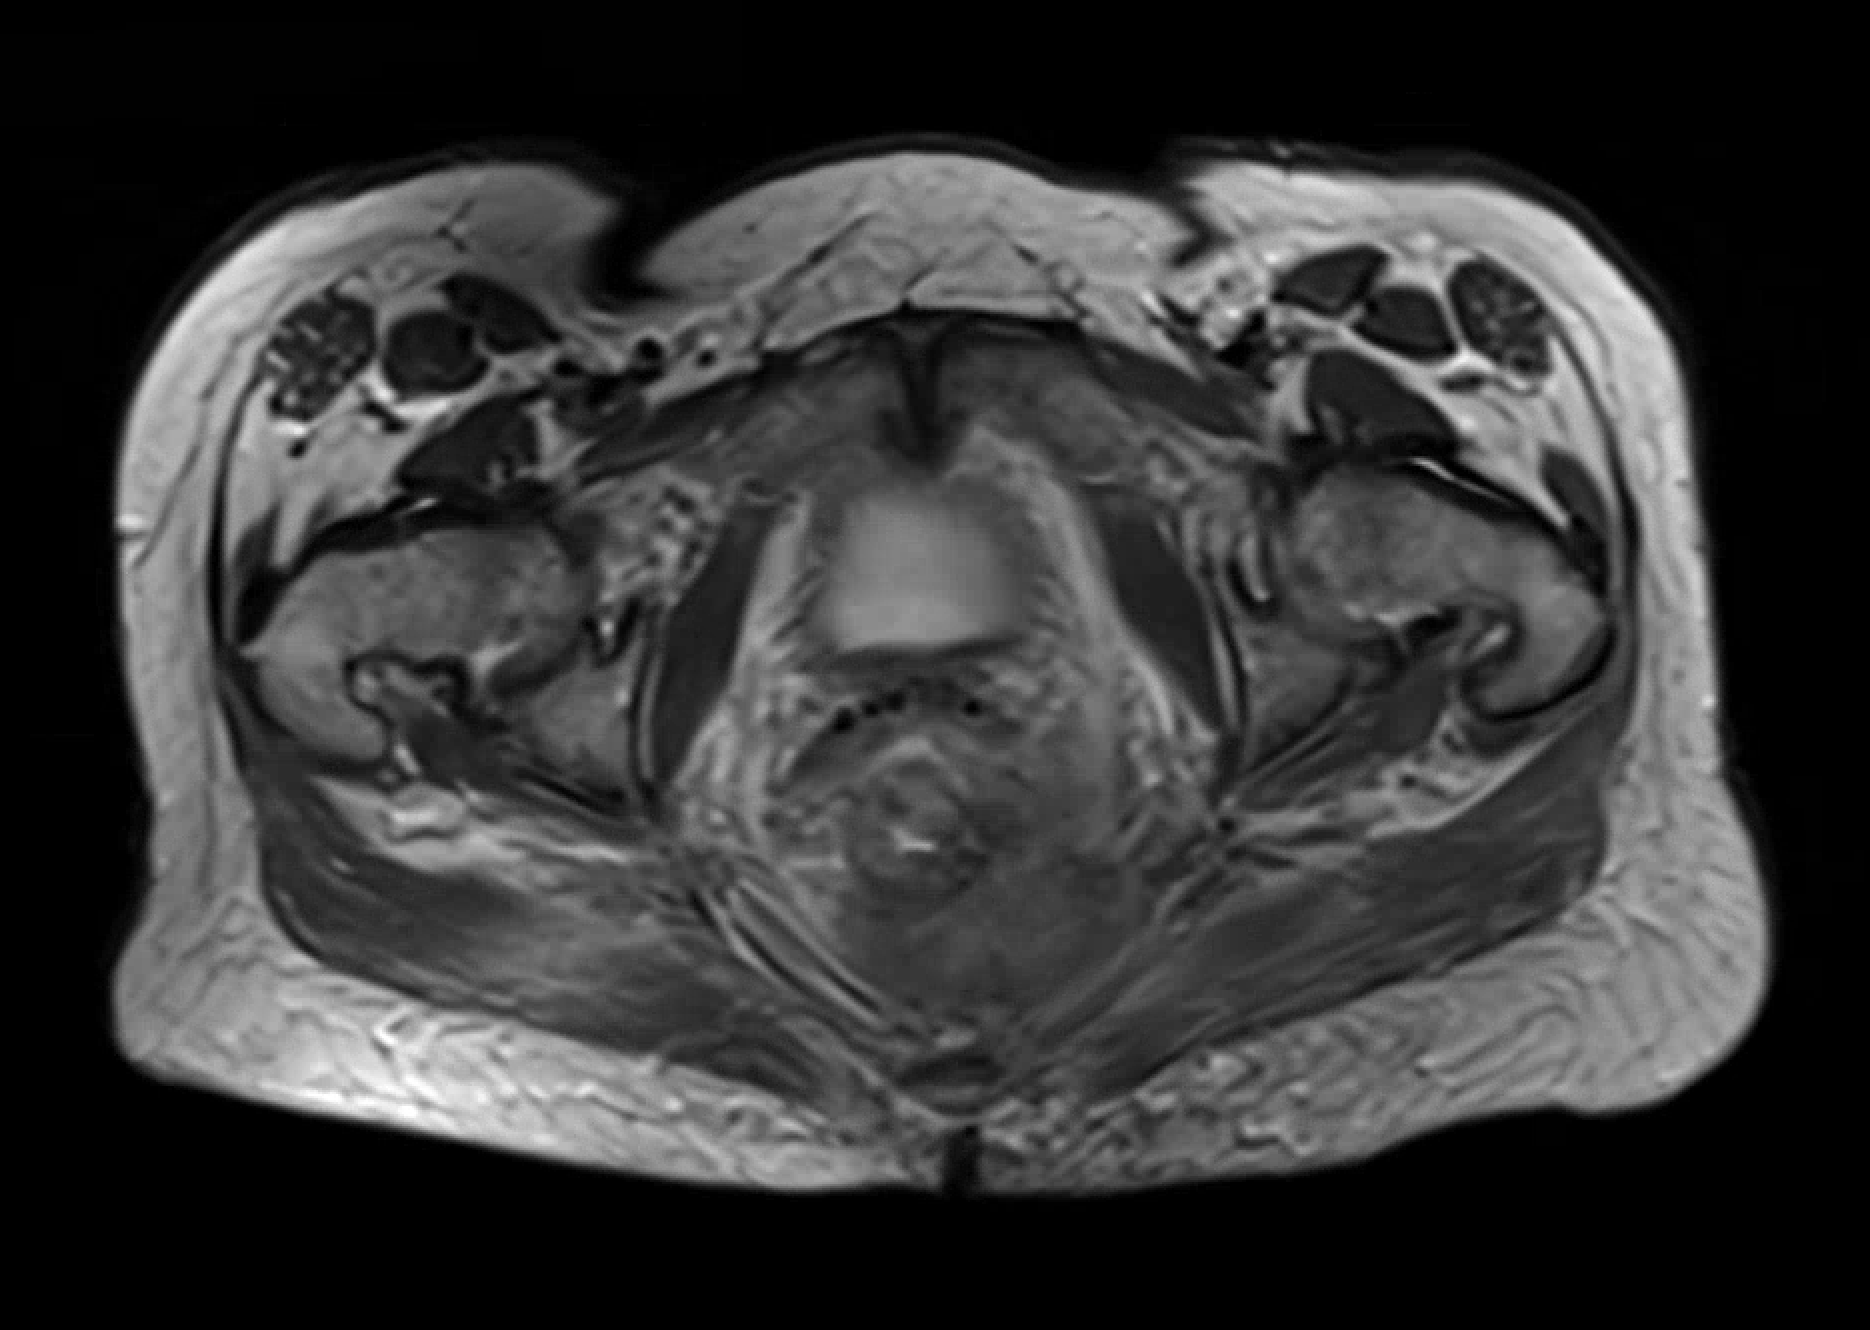

Pelvic MRI showing local invasion into mesorectum and left levator ani muscle with associated pelvic adenopathy